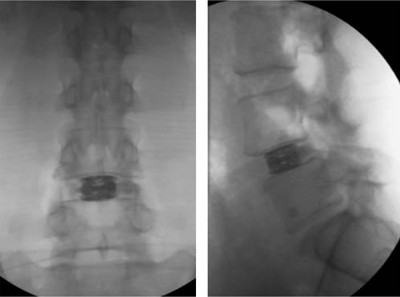

Control radiològic final de l’implant expandit